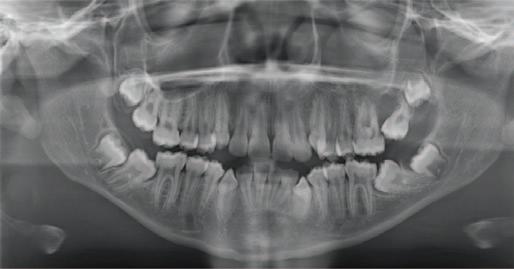

Daniel and Kayla are seven-year-old twins. They live with their parents in an estate in a large town. They are both outgoing and busy children. They enjoy school and activities with their friends. Daniel has mild autism. He has a special needs assistant in his classroom who helps him with his reading and language activities.

Daniel and Kayla have had uneventful visits to their family dentist once a year since infancy. Their teeth are brushed twice daily by their father. It is more challenging for Daniel as he does not always cope well with the flavour of the toothpaste. Recently, Daniel has found it more difficult due to sensitivity. Their dentist advised that Daniel has molar incisor hypomineralisation (MIH) and there was enamel breakdown on his newly erupted lower first permanent molars. Kayla’s teeth appeared normal. Bitewing radiographs showed that Kayla’s teeth were intact, but there were uncavitated lesions evident on Daniel’s primary molars.

Total 6; High*

*Even though the numerical score is 2, Daniel has a high risk of developing caries when considering the overall caries balance. This is due to the presence of MIH and the sensory challenges experienced in this case due to autism.

Actions:

Communicate risk to Daniel’s parents. Provide information regarding MIH. Advise continuing to brush Daniel’s teeth twice daily. Suggest unflavoured F toothpaste, e.g., Oranurse. Consider diet diary to provide tailored dietary advice. Plan and agree acclimatisation and preparation for Daniel’s future visits.